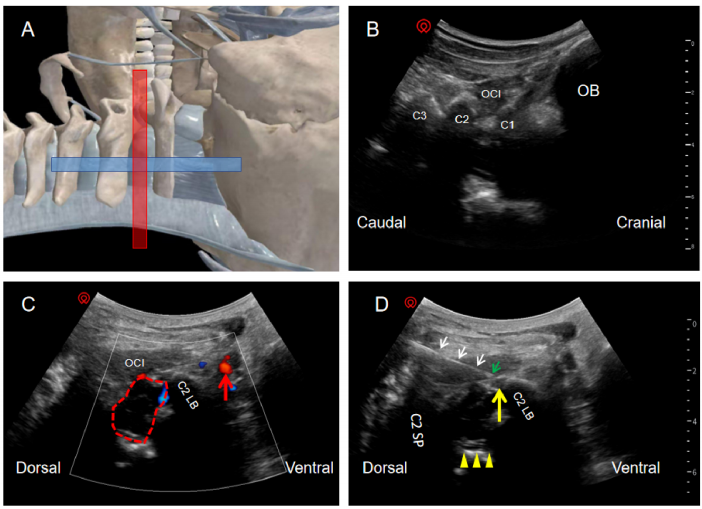

超声探头摆放的位置和对应超声图像

(A)超声探头摆放的位置。(B)颈椎矢状位的超声图像。(C)颈椎轴位的彩色多普勒图像。(D)超声引导穿刺图像。OB,枕骨;C1,寰椎的后弓;C2,枢椎的椎板;C3,C3椎板;OCI,头下斜肌;C2LB,C2椎体侧块;C2SP,C2棘突;红色线段,颈段脊髓;红色箭头,椎动脉;白色箭头,针体;绿色箭头,针尖;黄色箭头,颈2背根节;黄色三角箭头,硬膜囊前间隙。